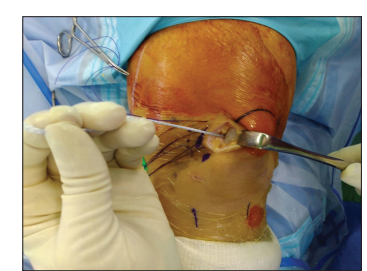

Một lưỡi cạo (shaver) 4,0 mm được sử dụng để cắt lọc và chuẩn bị bề mặt bám của MPFL trên bánh chè [Hình 1]. Sau khi chuẩn bị xong bề mặt, camera được chuyển sang cổng dưới trong. Một neo chỉ hoàn toàn 2,9 mm có hai sợi (Q-Fix™, Smith and Nephew) được đặt vào mặt trong của bánh chè qua cổng trên trong, dưới quan sát nội soi.

Kim tủy sống được sử dụng để đưa các vòng polydioxanone vào khớp như một thiết bị luồn chỉ — vật liệu dễ tìm và ít gây tổn thương mô mềm. Bốn vòng polydioxanone được chuẩn bị sẵn ngoài da, cách bờ trong của bánh chè khoảng 2,5 cm, sau đó được đâm vào khớp xuyên qua phần MPFL còn nguyên vẹn dưới quan sát trực tiếp qua nội soi, nhằm đảm bảo bắt đủ mô để phục hồi [Hình 2].